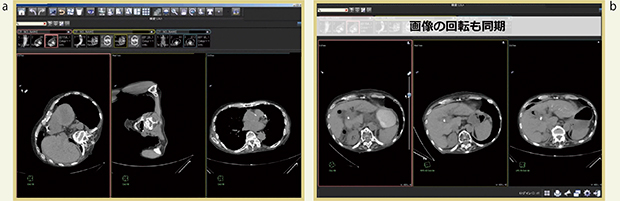

そこで,AZE Phoenixのスマートタグ,ハンギングプロトコル,ボリュームレジストレーションを使ったところ,読影が非常に容易になった(図1)。あらかじめ乳腺MRI用にハンギングプロトコルを設定しておけば,必要なシリーズの抽出,並べ替え,腹臥位から仰臥位への回転が自動で行われる。また,ダイナミック撮像の画像をスキャン順に並べる作業も自動化しており,キー画像を決めてボリュームレジストレーションすると,最も良く濃染しているシリーズを簡単に見つけることができる。各画像は拡大や移動も同期するため,従来は手動で行っていた作業の大部分を自動化でき,ストレスなく読影することができる。さらに,任意の断面表示も同期するため,各断面の観察を容易に行え,診断精度向上にもつながる。

図1 乳腺MRIの読影

a:従来は,必要なシリーズの抽出と並べ替え,さらに各画像の回転をすべて手作業でしなければならなかった。 b:AZE Phoenixでは,瞬時に必要な画像を必要な条件で表示でき,ボリュームレジストレーションで位置合わせ,拡大・移動の同期が可能となった。